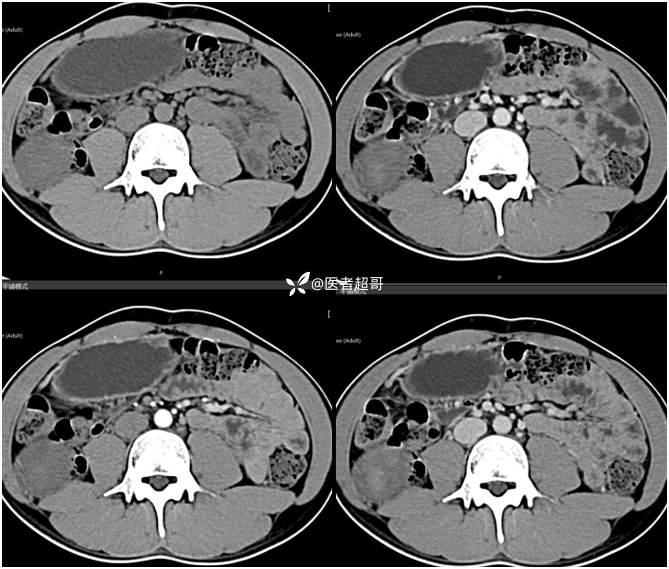

【影诊笔记754】腰痛就诊,腹膜后实性占位,请诊断分析!

主 诉:腰痛2月。

现病史:患者2月前无明显诱因出现腰背部疼痛,夜间为著。患者无头痛、头晕,无恶心、呕吐,无胸闷、憋气,无腹痛、腹胀。无尿频、尿急、尿痛等现象。患者在院外未作特殊治疗。为求进一步诊疗,来我院肾内科门诊就诊。门诊行双肾、输尿管、膀胱(前列腺)彩超提示:腹膜后实性占位。患者遂来我科就诊。我科以“腰痛”收治入院,患者自发病以来,神志清,精神可,饮食可,睡眠差。小便如上述,大便未见明显异常。体重无明显增减。